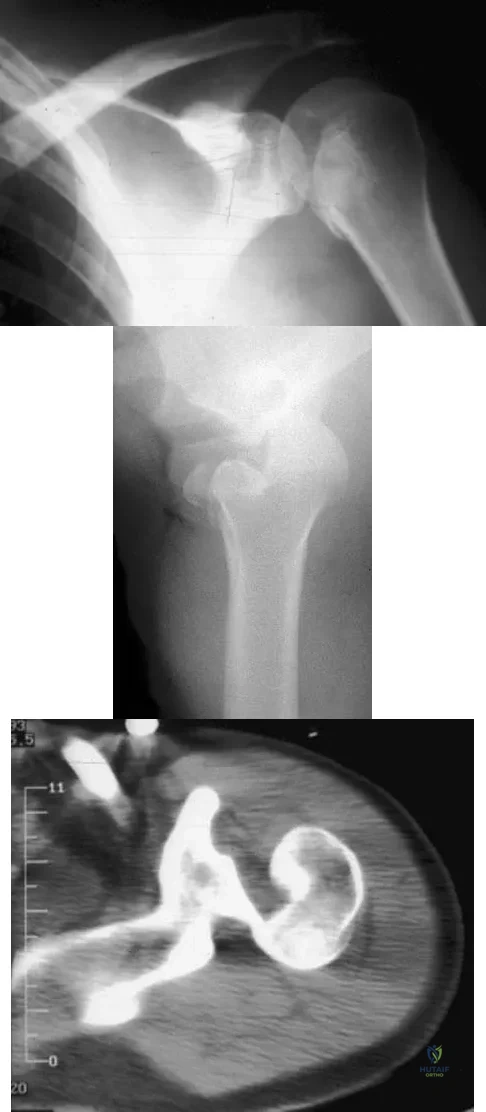

Question 47

A 21-year-old patient has had pain and a marked decrease in active and passive shoulder motion after having had a seizure 2 months ago as the result of alcohol abuse. Current AP and axillary radiographs and a CT scan are shown in Figures 26a through 26c. Management should consist of

Explanation